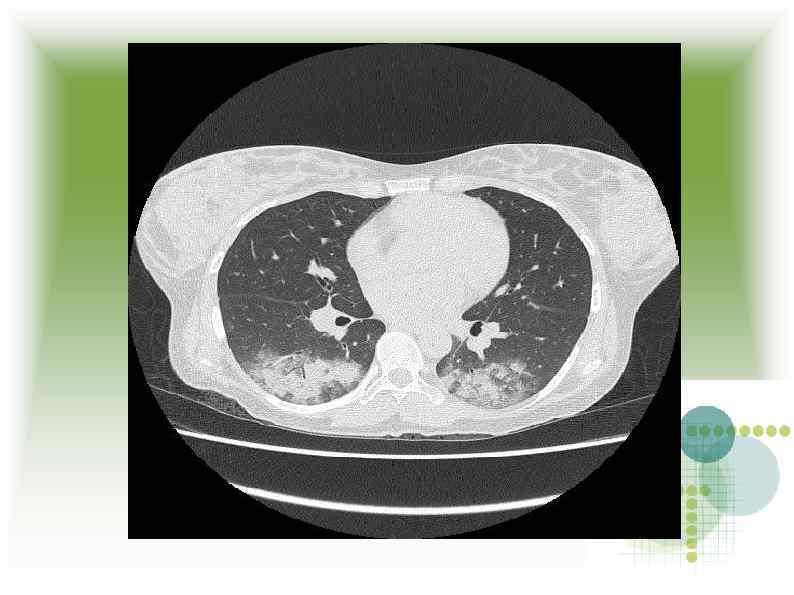

МСКТ МСКТ

Заключение МСКТ Признаки геморрагической пневмонии? Заключение МСКТ Признаки геморрагической пневмонии?